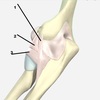

221

radial collateral ligament

2

223

lateral ulnar collateral ligament - holds the ulna in place

225

annular ligament